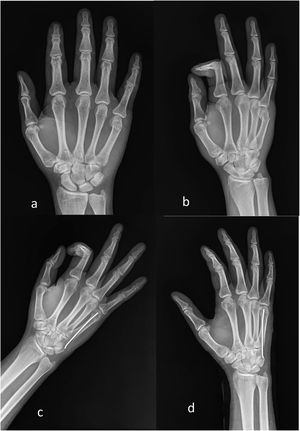

Material and methodsAn observational, prospective study was carried out in a tertiary hospital, after being approved by the local Ethics Committee of the Mexican Social Security Institute (R-2017-2105-27), including patients with FFMN with an evolution time of less than one week and treated by CRIMF via retrograde (Fig. 1) or antegrade (Fig. 2) with AK. Both are standard outpatient treatments in this hospital unit and the choice is at the surgeons’ discretion. Patients treated with other types of osteosynthesis material, open fractures, and patients stabilised for more than one week were excluded.